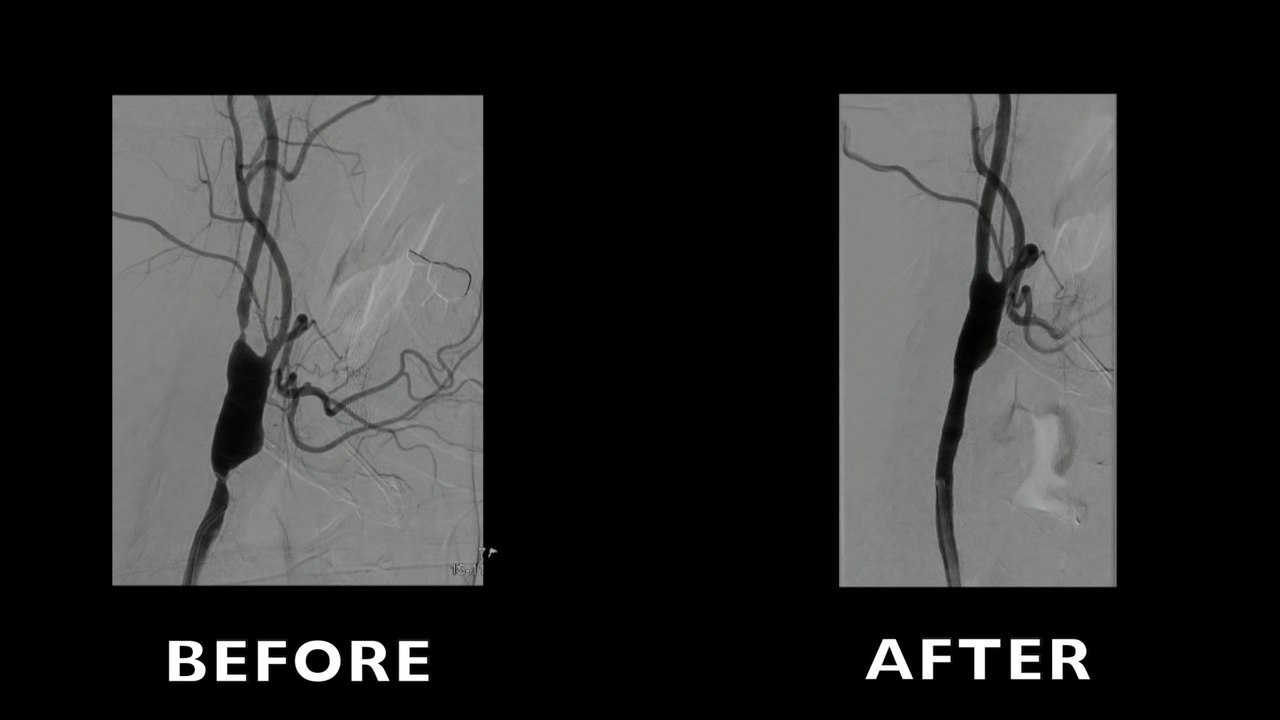

Carotid procedures: Improve your skills!

Improve your skills on carotid artery stenting procedures! You will be able to learn more about carotid artery access: femoral, brachial, radial.  Learn about carotid artery protection dur...